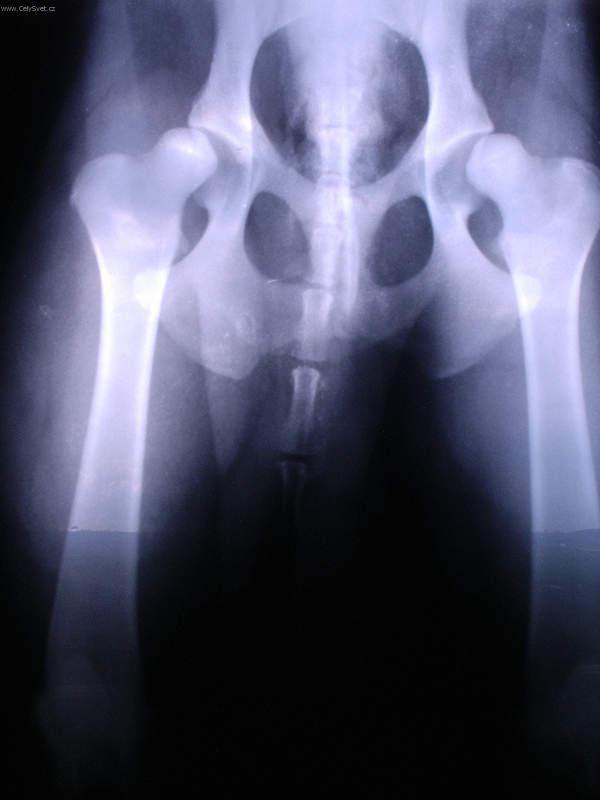

Fotogalerie > PSÍ SVĚT: Veterinární poradna > Ortopedie - DKK